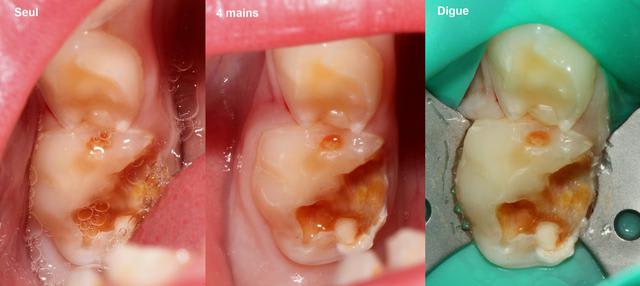

La digue est posée pour tous les traitements endodontiques et une RCPE (reconstitution coronaire pré endodontique, j'ai découvert l'acronyme en arrivant à Lyon) est réalisée par différentes techniques dès qu'il manque une paroi. Enfin jusqu'à l'année dernière (quand j'y étais) c'était comme ça. Je ne pense pas que ça ait changé à la rentrée.